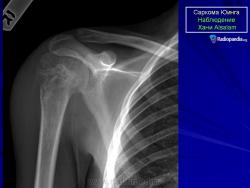

С Радиопедии.

Саркома Юинга грудной стенки.